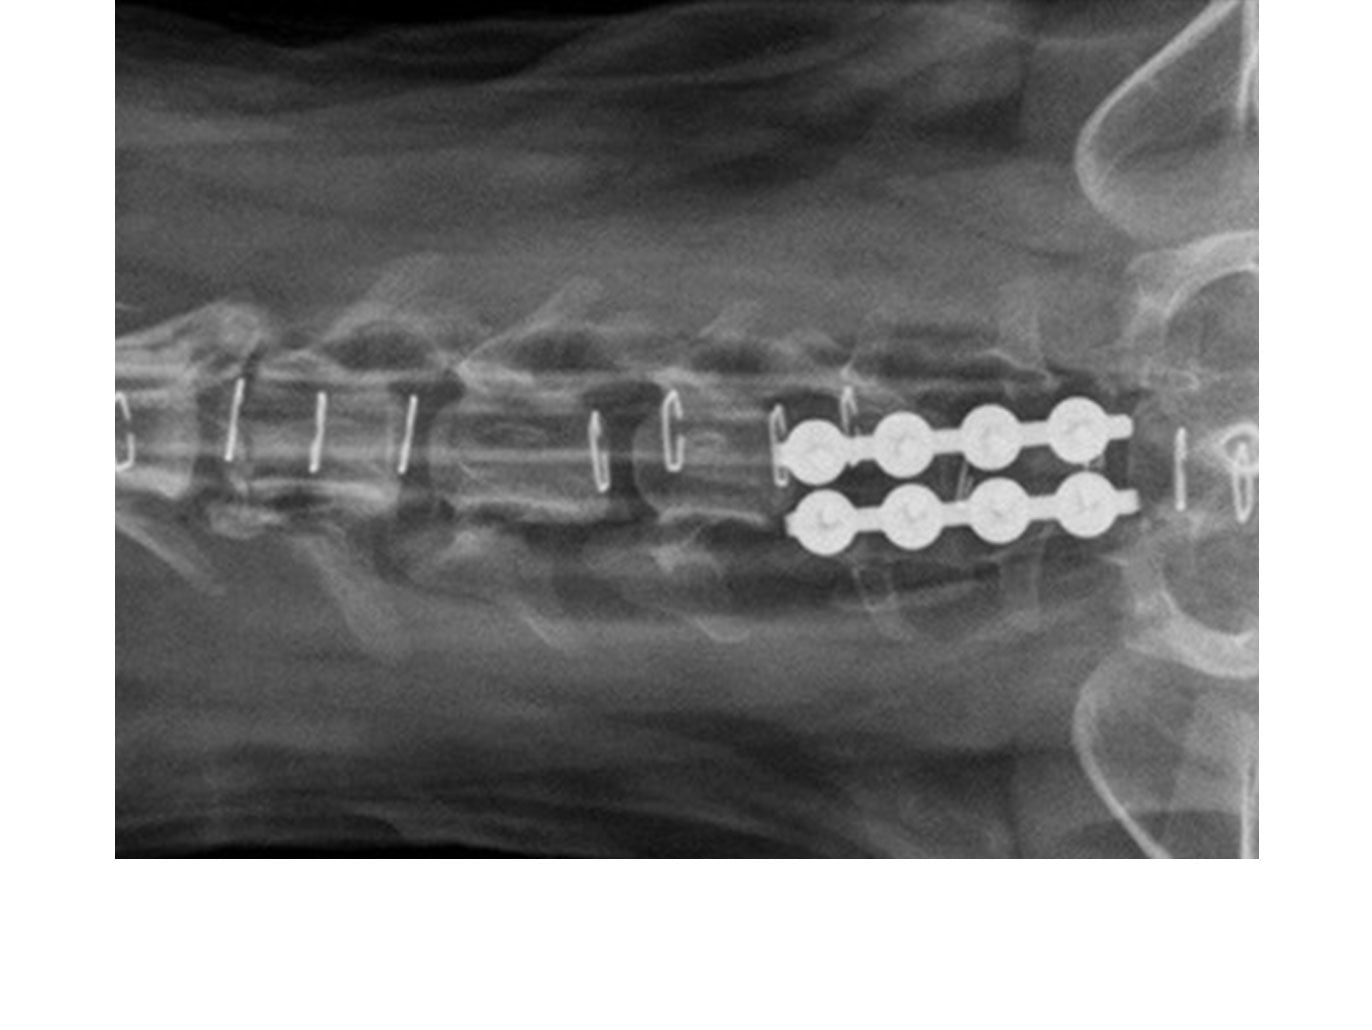

• Lumbo-sacral

SOP™ uniquely offers a spinal stabilization system with reasonable cost. The SOP™ plates are commonly used in pairs with the screws engaging vertebral pedicles or bodies. The SOP™ can be used similarly to a pedicle screw system for the thoracolumbar spine, or as a locking anterior system for cervical stabilisation/fusions.

// User Cases

Highlighting the cases of these products in real-life situations is vital to demonstrating their success. Below are cases studies of long-term follow up surgeries.